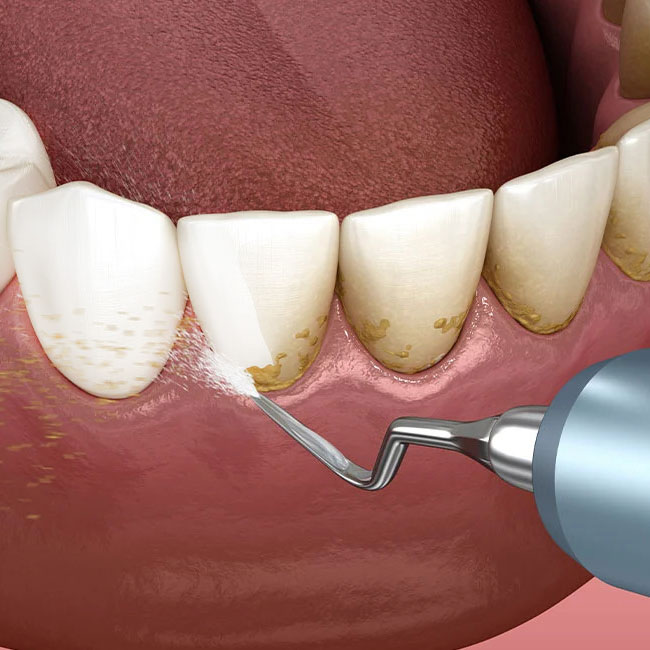

جرمگیری دندان یکی از روش های برای حفظ بهداشت و سلامتی دهان و دندان است. در کلینیک دکتر آزیتا خورشیدیان، ما از ابزارهای پیشرفته مانند اسکالر اولتراسونیک، ابزارهای دستی دندانسازی و پروفایلر پالیشینگ استفاده میکنیم تا تمام پلاک دندانی، تارتار و رسوبات معدنی از سطح دندانها حذف شود.

این فرآیند نهتنها از بروز پریودنتیت، ژنژیویت (Gingivitis) و پوسیدگیهای دندانی جلوگیری میکند، بلکه به بازسازی مینای دندان و حفظ سلامت اکلوژن و فیشورهای دندانها کمک مینماید. با رعایت دقیق استانداردهای بهداشتی و تخصصی، لبخند شما پس از هر جلسه جرمگیری سالم، درخشان و زیبا باقی میماند.